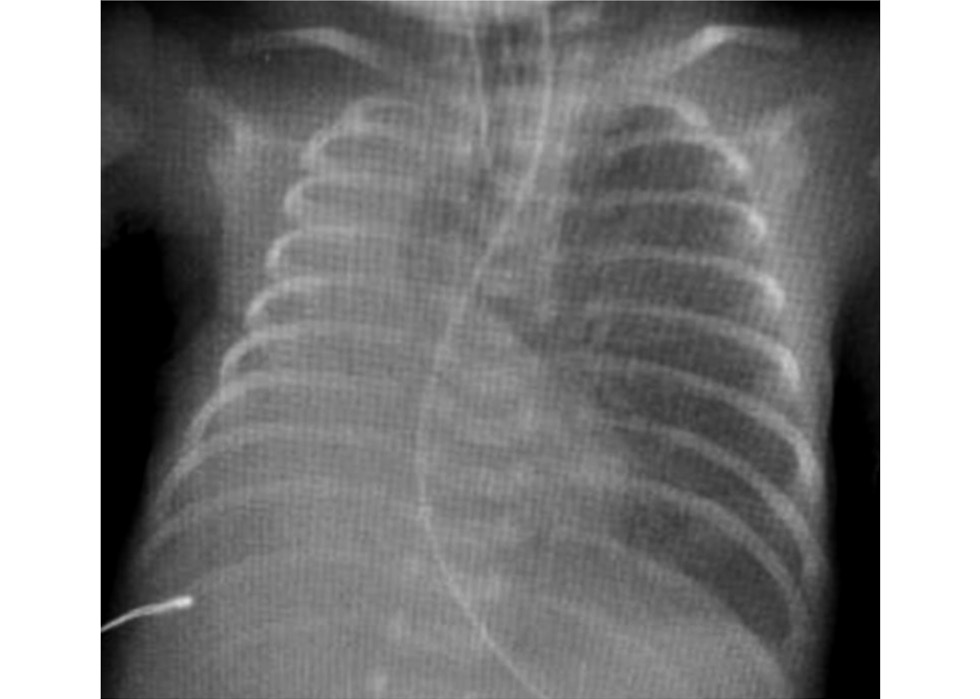

На 2 сут жизни дети были переведены в неонатальный центр на базе Детского городского многопрофильного клинического специализированного центра высоких медицинских технологий (ДГМКСЦ ВМТ) г. Санкт-Петербурга. Состояние больной требовало высокочастотной вентиляции лёгких, массивной антибактериальной терапии препаратами резерва, коррекции гипокоагуляционного синдрома и анемии. По совокупности анамнестических, клинических и лабораторных данных зарегистрирован ранний неонатальный сепсис, респираторный дистресс-синдром с выраженным снижением пневматизации обоих лёгких (рис. 1). По данным эхокардиографии выявлены открытый артериальный проток и высокая лёгочная гипертензия. К терапии добавлены ингаляции оксида азота. По данным нейросонографии выявлены внутрижелудочковые кровоизлияния 3 степени слева и 2 степени справа. Больная обследована на течение внутриутробной инфекции: выполнены анализы крови на выявление цитомегаловируса, герпес вирусов 1 и 6 типа, микоплазмы и уреаплазмы методом полимеразной цепной реакции (ПЦР) — результаты отрицательные.

Рис. 1. Рентгенограмма органов грудной полости при поступлении (2 сут жизни).

Fig. 1. Second day of life, сhest X-ray at admission.